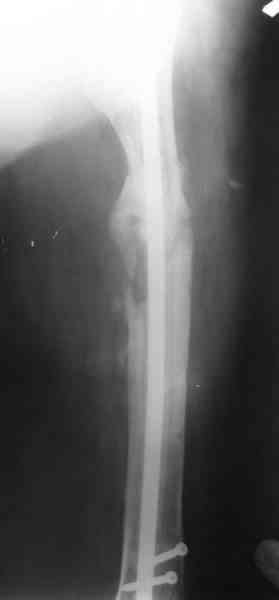

В настоящее время наш пациент ( см. http://weborto.net/forum/1177351385/) ходит с одним костылем. У него периодически открывается свищ на задне-наружной поверхности бедра с умеренным серозно-гнойным отделяемым. Температура тела и анализы нормальные. На рентгенограммах имеются признаки консолидации ложного сустава.

1, 2, 3, 4 - рентгенограммы бедра от 8 августа этого года (через четыре месяца после операции);

В качестве демонстрации лечения канального остеомиелита бедренной кости представляем пациентку (см. parts 2 и 3), которая как раз сегодня была у нас на контрольном осмотре. В мае этого года мы произвели ей фиксацию бедренной кости штифтом-спейсером по поводу ложного сустава и канального остеомиелита бедренной кости. Через 4 недели после операции свищи закрылись. Сейчас она ходит с полной нагрузкой на конечность.

4, 5, 6 - рентгенограммы бедра и фотографии пациентки (прошу прощения за низкое качество рентгеновских снимков) от 7 сентября 2007 г.